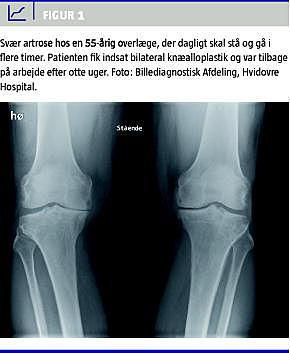

Gennemgående i litteraturen er, at præoperativ sygemelding eller arbejdsløshed indikerer en forringet chance for at returnere til arbejdsmarkedet - både hvad angår THA og TKA, hvorimod de, som er i arbejde præoperativt, for over 90%'s vedkommende returnerer til deres arbejde postoperativt (Figur 1 ) [5, 6, 18-23]. I et dansk THA-studie fra 1985 af Jensen et al fandt man, at 85% af de patienter, der oppebar invalidepension præoperativt, var plaget af smerter postoperativt, mens dette kun gjorde sig gældende for 8% af pensionisterne og for kun 1% af de patienter, som præoperativt var i arbejde [5]. I flere studier, inkl. førnævnte, er der vist en langt større tilfredshed med resultatet hos de patienter, som postoperativt var i arbejde [5, 20].